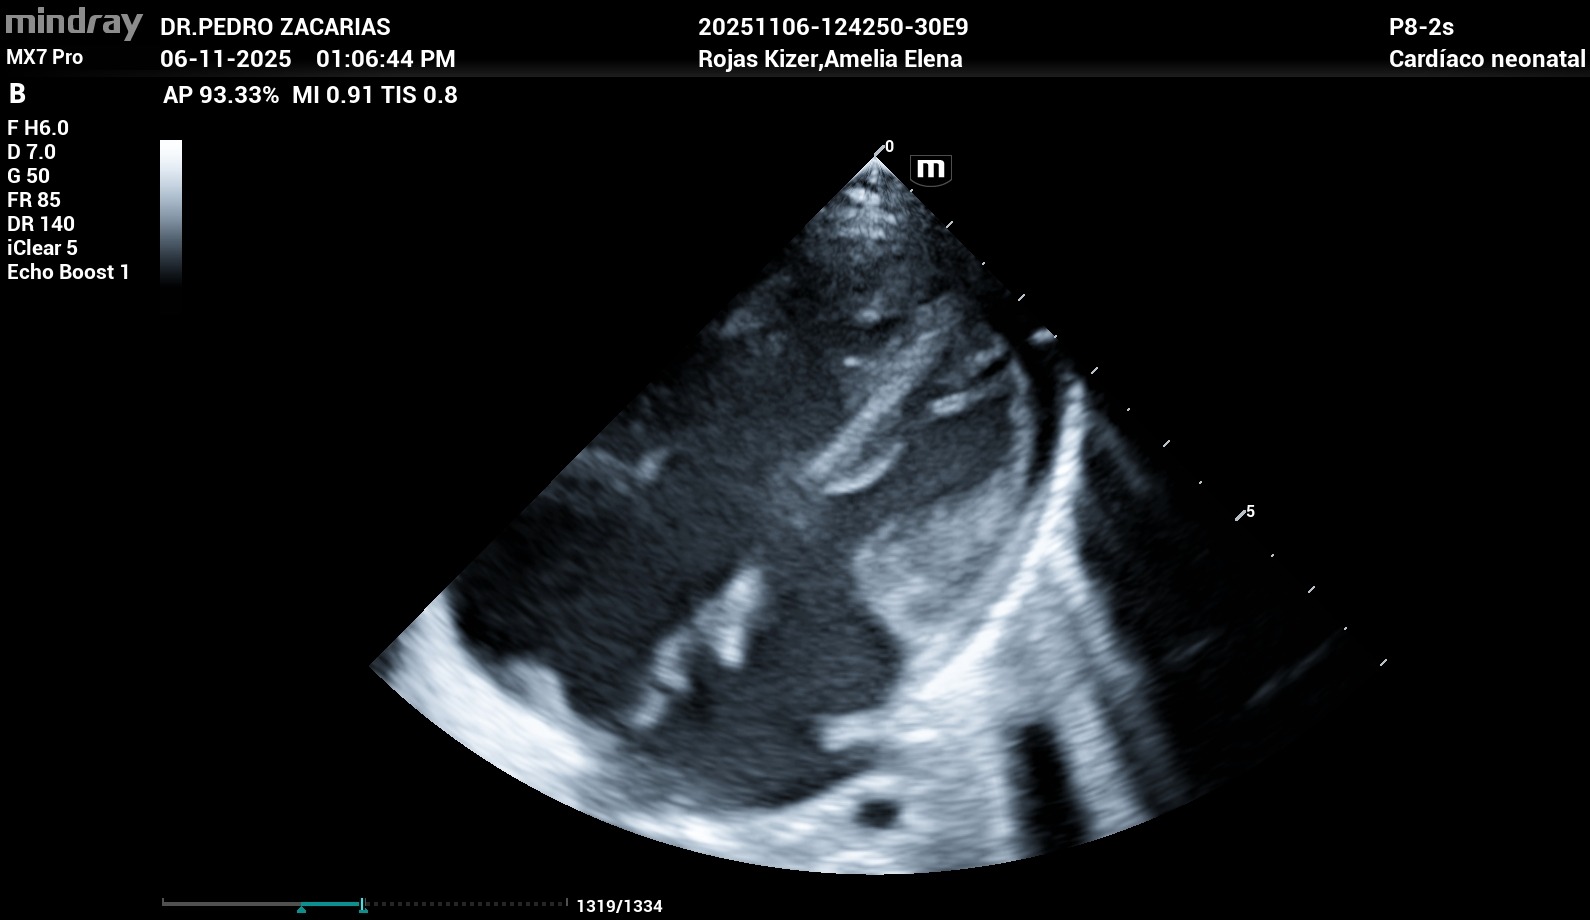

Al mes de nacida fue diagnosticada con una cardiopatía congénita compleja: Canal Auriculoventricular Completo Rastelli tipo A, además de otras malformaciones cardíacas como PCA, CIV y CIA. Estas condiciones hacen que su pequeño corazón no se haya formado correctamente y hoy tenga que trabajar el doble para mantenerla con vida.